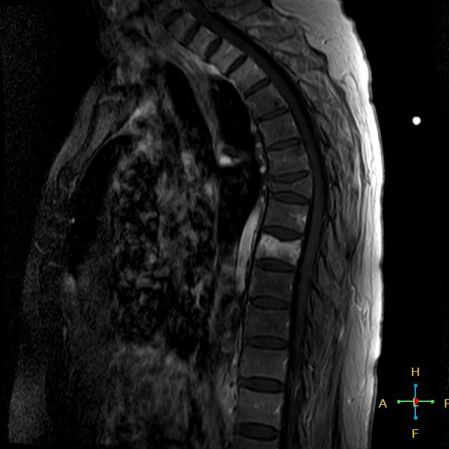

——良性压缩性骨折MR信号特点—— 良性骨折的修复过程:缺血性变化--修复(骨髓水肿、血流增加或充血现象)--修复近完成(血流恢复正常)--慢性期(脂肪组织再生)。 正常成人:椎体为黄骨髓,T1WI 、T2WI 均为高信号。 当骨髓内出现水肿时,T1 低信号, 与残余的正常骨髓形成明显对比,所以椎体压缩骨折后,MR 信号改变以 T1WI 上观察最好;而在常规 T2WI 图像上,病变骨髓的长 T2 高信号与正常骨髓脂肪信号差别较小,不易观察;T2WI 脂肪抑制技术对于突出显示骨折区长 T2 组织信号具有独特优势,对于判断椎体是否发生脂肪变及骨折是否愈合也有一定价值。 急性早期,椎体压缩,局部缺血,骨髓水肿,T1WI 不均匀低信号,T2WI 高信号,增强扫描无明显的强化。 随后,骨折部位开始修复,血流量增加,增强扫描可出现明显的强化,平扫信号无改变。 慢性期,骨髓内脂肪组织再生,T1WI 椎体内呈混杂高信号。

由于大多数外力轻微,椎体内多形成范围局限、移位不明显的骨折线,骨折线周围水肿亦多局限,因此,较少出现全椎体信号异常。

椎体后角回避现象:T1WI 椎体上部或大部呈低信号, 而后角信号不变。

椎弓根改变:由于旋转的扭力或是上下的压力造成椎体血流循环改变而致椎弓根的髓内水肿,使信号改变累及椎弓根,但椎弓根无变形或膨大。

——恶性压缩性骨折MR信号特点—— 由于肿瘤组织的侵犯,T1WI上椎体呈弥漫性低信号,T2WI呈高信号,增强扫描呈明显不均匀强化。